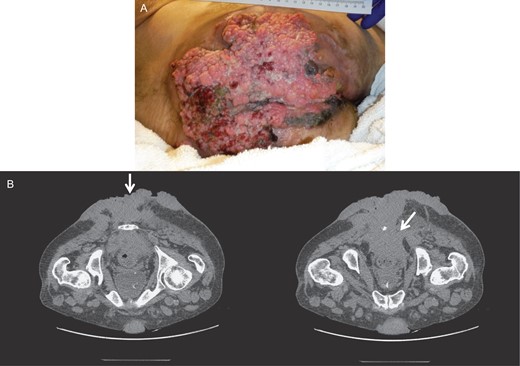

However, ~6 weeks later, he was readmitted due to regrowth of the invasive anal condyloma. All of the areas previously quiescent and clean of tumor were full of new lesions, extending into the pelvic sidewall and the anorectal region, as well as the area of excision. The lesions deteriorated with necrosis, foul odor, and abscesses over time, and debridement and drainage were performed mostly to manage the wound and reduce septic risk (Fig. 4). Multiple readmissions for secondary infections and peri-lesion abscesses occurred for months.

Gross image (A) and CT of the pelvis and perineum (B) showing tumor recurrence.